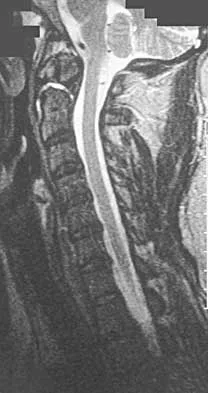

Question 23

A 42-year-old woman reports that she has low back pain and had a transient loss of consciousness after falling off a horse. She denies having neck pain but notes that she was involved in a motor vehicle accident 2 years ago and had neck pain at that time. Examination reveals full range of motion of the neck and no localized tenderness. The neurologic examination is normal. A lateral radiograph of the cervical spine is obtained. Figures 41a and 41b show CT and MRI scans. What is the most likely diagnosis?

Explanation

The examination findings do not correlate with an acute injury (full range of cervical motion and the absence of pain). Radiographically, the fracture appears old based on the smooth contour of the fracture fragments and the absence of soft-tissue swelling. Flexion-extension radiographs can be obtained to determine potential instability; if present, stabilization and fusion should be considered. Schatzker J, Rorabeck CH, Waddell JP: Non-union of the odontoid process: An experimental investigation. Clin Orthop 1975;108:127-137.